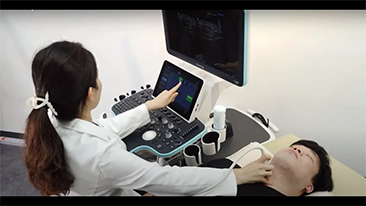

Resona 7

Desde que a empresa foi fundada, a Mindray est├Ī continuamente explorando novas maneiras de melhorar a confian?a no diagn├│stico. Alimentada pela mais revolucion├Īria tecnologia ZONE Sonography?, a nova plataforma Resona 7's ZST+ traz uma qualidade de imagem ultra-som a um n├Łvel superior por aquisi??o de zona e processamento de dados do canal.

Assim como o n├Łvel de qualidade de imagem premium, o Resona 7 tamb├®m melhora as capacidades de investiga??o cl├Łnica com o revolucion├Īrio Fluxo V para avalia??o hemodin?mica vascular e a aquisi??o de plano mais inteligente do conjunto de dados 3D para diagn├│stico CNS fetal. Combinando a opera??o mais intuitiva baseada em gesto de multi-toques e todos os recursos cl├Łnicos essenciais, Resona 7 est├Ī realmente conduzindo novas ondas na inova??o de ultra-som.